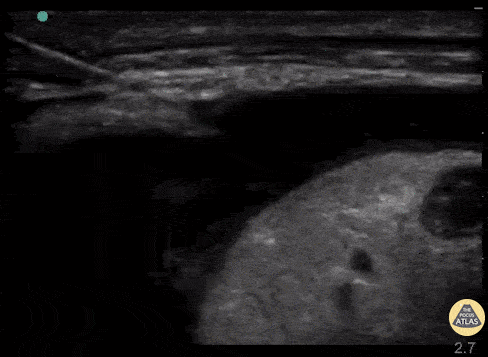

Dynamic needle guidance in a parasternal view used to perform an emergent pericardiocentesis in a hemodynamically unstable patient. Ahad Al Saud, Emergency Medicine Physician @Ahad_AlSaud